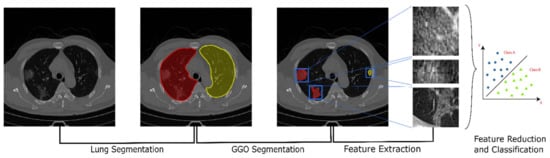

2.2. Pipeline Overview

The workflow developed in this work as show in Figure 1 can be split into 3 steps: (1) the segmentation of the lungs; (2) segmentation of the GGO areas; (3) estimation of the radiomic features.

Figure 1. A schematic representation of the proposed pipeline. From the left: raw CT scan; segmentation of the two lungs using a pre-trained U-Net model; segmentation of the GGO areas using k-means clustering; extraction of radiomic and Haralick features; classification and prediction of the clinical characteristics and outcomes.